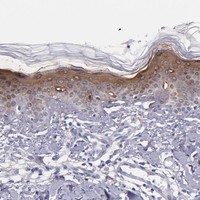

Enhanced - Orthogonal

Antibody staining mainly consistent with RNA expression data across 44 tissues.

HIGH EXPRESSION

Skin 1

RNA expression: 155.9 nTPM